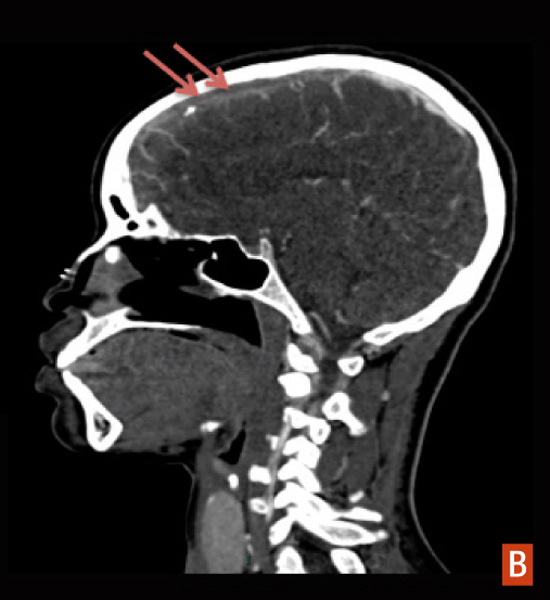

Hématome lobaire frontal bilatéral

Hématome lobaire frontal bilatéral : angioscanner veineux, défect dans le sinus sagittal supérieur.